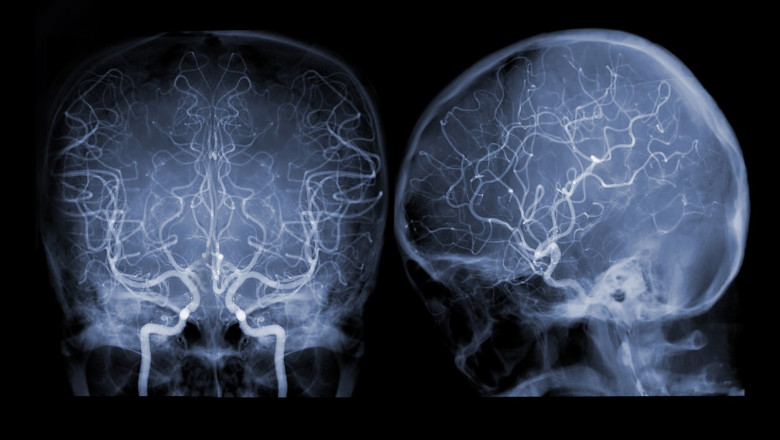

Medicii au descoperit, prin tehnica de imagistică prin rezonanţă magnetică (RMN), o „leziune atipică” în partea frontală a creierului australiencei în vârstă de 64 de ani.

Parazitul, a cărui „structură asemănătoare unui fir” a apărut în imaginile obţinute în urma unui RMN cerebral, a fost identificat ulterior prin teste ADN.